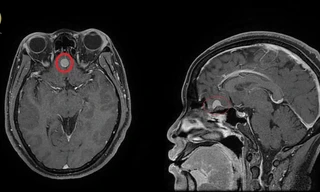

Cảnh giác phát hiện u màng não từ biểu hiện đau đầu thường xuyên

Đau đầu là triệu chứng phổ biến, thường gặp có thể do nhiều yếu tố gây nên như thiếu ngủ, căng thẳng thần kinh, tiếp xúc tiếng ồn, thay đổi thời tiết... Tuy nhiên, nếu có biểu hiện đau đầu thường xuyên thì hãy đi khám ngay bác sĩ, bởi đó có thể là biểu hiện của tổn thương, bệnh lý nguy hiểm trong não.